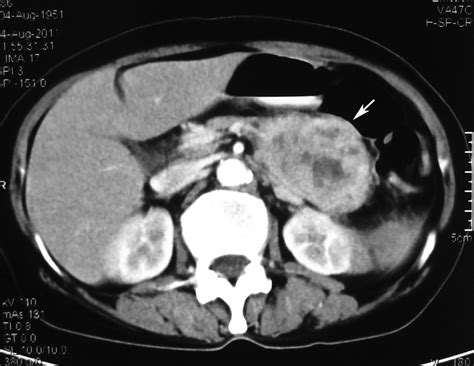

Как проводится КТ при IPMN поджелудочной железы